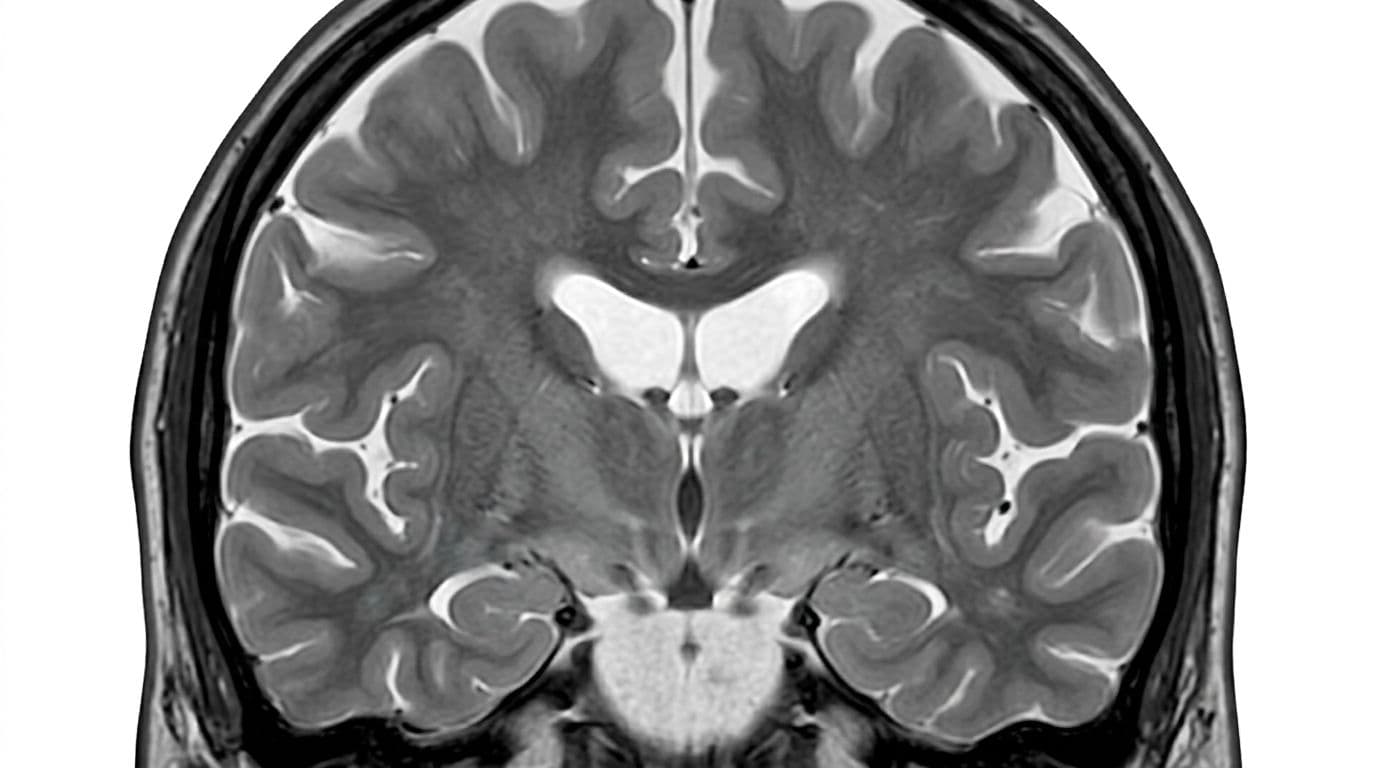

An MRI-style view showing how mild dehydration can change measured brain volume, created with AI.

Your brain is water-rich, and it reacts fast to changes in body water. When you're low on fluids, MRI scans can show small shifts in brain volume and changes in the fluid-filled spaces inside the brain (the ventricles). Think of it like a grape that's slightly less plump, not a raisin.

In dehydration research, "brain shrinkage" usually means a small drop in measured brain volume on MRI after a period of fluid restriction. Several papers report changes in the ballpark of 0.3% to 0.6% after roughly 12 to 16 hours of mild dehydration.

Researchers also often see the ventricles expand a bit. That makes sense, because if brain tissue holds slightly less water, the fluid spaces can look a little larger. One place to explore the details is this open-access review of acute dehydration and brain morphology on the NIH site: acute dehydration effects on brain structure (NIH PMC).